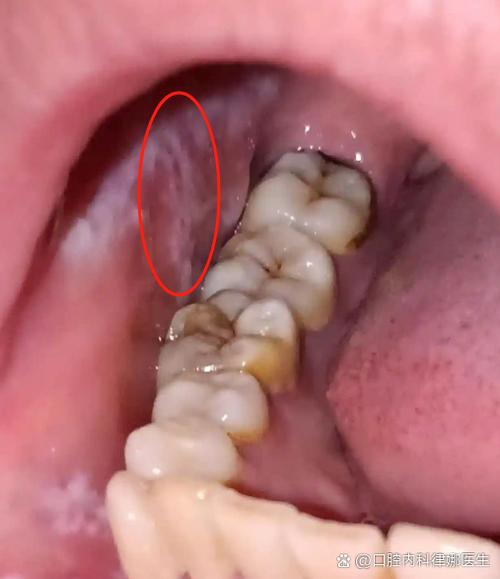

扁平苔藓

一种原因不明的慢性炎症性皮肤病,也可累及口腔黏膜,口腔扁平苔藓的皮损有多种形态,其中一种就是网状或斑片状的白色条纹(Wickham纹)。

- 特点:

- 通常伴有轻微的灼痛或粗糙感,但有时也可以是无症状的。

- 白色条纹常呈“树枝状”或“网状”,周围黏膜可能正常或发红。

- 有一定的癌变风险,需要定期随访。